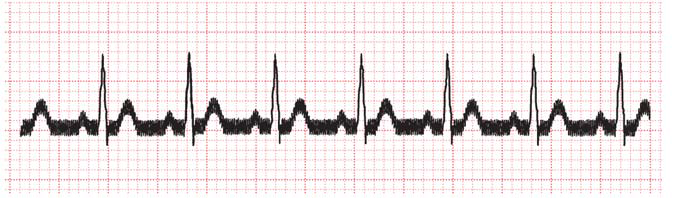

肌肉伪差

肌肉伪差通常因颤抖或帕金森病的引起阵颤导致,可移动肢体电极,使其接近肩膀或臀部,从而减少震颤对心电图信号的影响。将电极移近肩膀或臀部虽然会导致信号幅度略有下降,从而可能影响心电图结果的解读,但总体而言,这种调整反而会使心电图数据更易于分析。